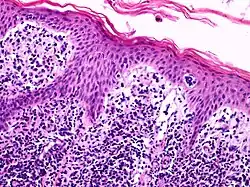

![]() A histological view of Lutzner cells surrounded by erythrocytes in a blood smear. | |

Lutzner cells were discovered by Marvin A. Lutzner, Lucien-Marie Pautrier, and Albert Sézary. These cells are described as the smaller forms of Sézary cells, or Sézary-Lutzner[1] cells, and the two variants are recognised as being morphologically different. Aggregates of these cells in mycosis fungoides are known as a Pautrier's microabscesses. They are a form of T-lymphocytes that have been mutated.[2] This atypical form of T-lymphocytes contains T-cell receptors on the surface and is found in both the dermis and epidermis layers of the skin. Since Lutzner cells are a mutated form of T-lymphocytes, they develop in bone marrow and are transported to the thymus is order to mature.[3] The production and maturation stages occur before the cell has developed a mutation. Lutzner cells can form cutaneous T-cell lymphoma, which is a form of skin cancer.[4]